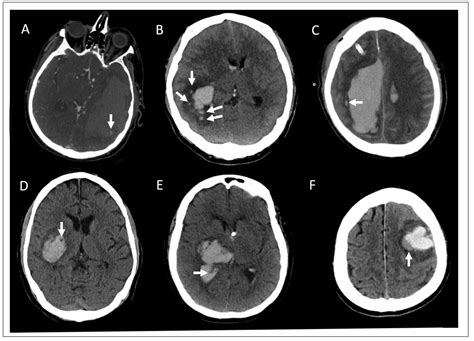

Diagnosing a Brain Haemorrhage

Diagnosing a brain haemorrhage typically involves a combination of clinical evaluation and imaging tests. Common diagnostic procedures include:

• Computed Tomography (CT) Scan: This imaging test provides detailed images of the brain and can quickly detect the presence of bleeding.

• Magnetic Resonance Imaging (MRI): This test uses magnetic fields and radio waves to produce detailed images of the brain, helping to identify the location and extent of the haemorrhage.

• Angiography: This procedure involves injecting a contrast dye into the blood vessels to visualize them and identify any abnormalities, such as aneurysms or arteriovenous malformations (AVMs).

Types of Brain Haemorrhages

Brain haemorrhages can be categorized into several types based on their location and cause:

• Intracerebral Haemorrhage (ICH): This type occurs when a blood vessel within the brain bursts, leading to bleeding directly into the brain tissue.

• Subarachnoid Haemorrhage (SAH): This involves bleeding into the subarachnoid space, the area between the brain and the tissues that cover it.

• Epidural Haemorrhage: This type occurs when blood accumulates between the skull and the dura mater, the outermost layer of the meninges.

• Subdural Haemorrhage: This involves bleeding between the dura mater and the arachnoid mater, the middle layer of the meninges.